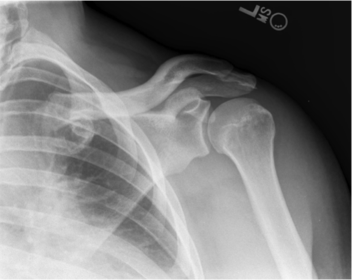

| AP Shoulder | patient is rotated towards the unaffected shoulder: decreased thoracic superimposition over the scapular body |

| AP Shoulder | patient is rotated towards affected side:increased thoracic superimposition over the scapular body |

| AP Shoulder Neutral | ANATOMY: proximal humerus, lateral 2/3 of clavicle, open shoulder joint CRITERIA: humeral epicondyles are 45 degrees to the IR neither tubercle should be seen on the humeral head POSITIONING: CR perpendicular @ 1'' inferior to coracoid process |